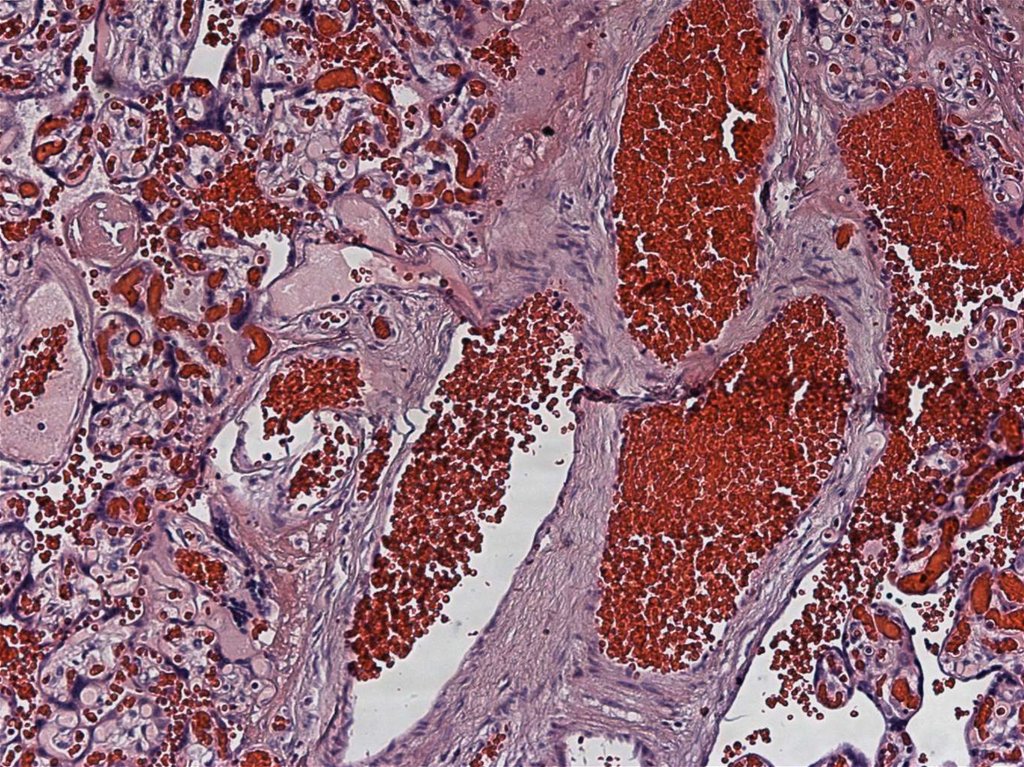

5.

доношенные

недоношенные

1

5

6

19

С ГИПОТРОФИЕЙ

С НОРМАЛЬНОЙ МАССОЙ ТЕЛА